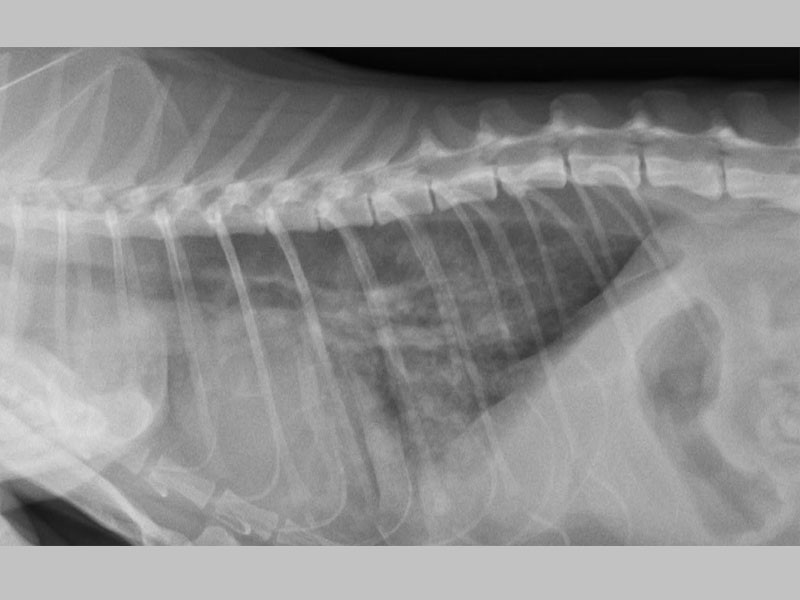

肺積水的胸腔X光

肺積水導致呼吸困難

肺積水導致呼吸困難的四歲貓咪--咪,緊急給氧及利尿後脫離危險,經超音波掃描診斷為擴張性心肌病,詳細詢問生活情況後發現為長期吃狗飼料所引起的心臟問題,這樣的心臟病是有機會痊癒的喔!!!!!

肺積水導致呼吸困難的四歲貓-咪咪,在築心緊急給氧氣治療及利尿後終於脫離危險,而進一步進行超音波掃描,診斷為擴張性心肌病,詳細詢問主人生活情況後發現有長期吃狗飼料的問題,提醒毛爸毛媽,貓咪相對狗狗需要較多的脂質和蛋白質,狗狗飼料無法給予貓咪足夠的營養,長期下來可能會造成眼睛失明、耳聾或心臟病等疾病問題。然而這種情況下所引起的心臟病,是有機會痊癒的!所以建議有任何心臟疾病問題的毛小孩,一定要由專業的醫師及專門的心臟超音波設備來檢查、確診,才可以更加了解毛小孩的身體狀況而對症下藥喔!